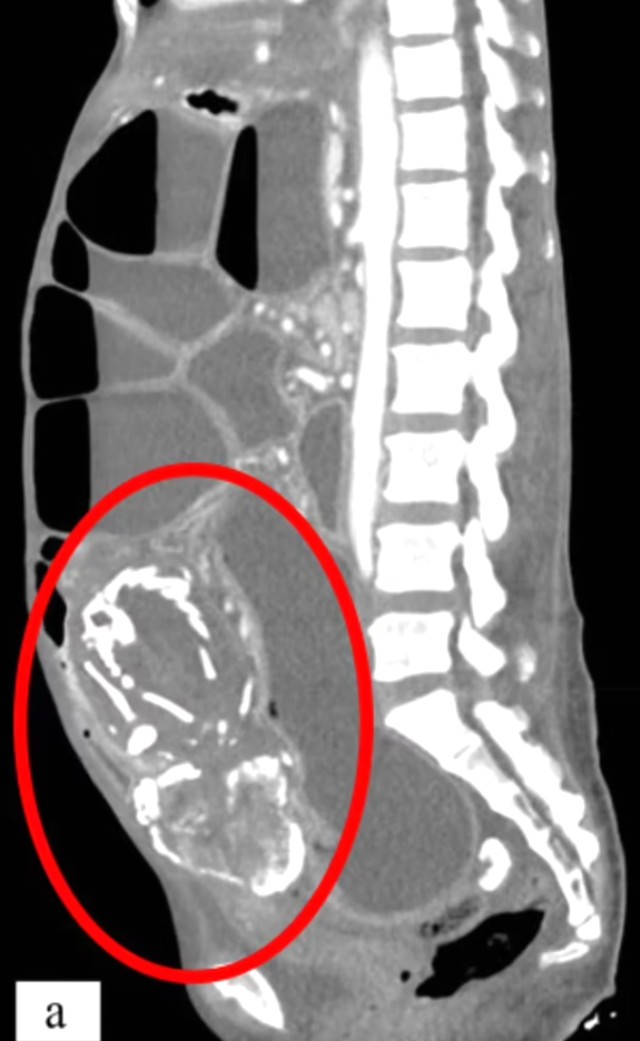

Belə ki, 9 il əvvəl qadının bağırsaqlarında uşaqlıq yerinə döl əmələ gəlib və bu döl zamanla daşa çevrilərək bağırsaqlarını bağladığı üçün onun ölümünə səbəb olub.

Hadisə ilə bağlı açıqlama verən Dr. Waseem Sous, 50 yaşlı qadının daha əvvəl şikayətləri olduğunu, lakin əməliyyat olunacağından qorxaraq müalicədən imtina etdiyini bildirib.